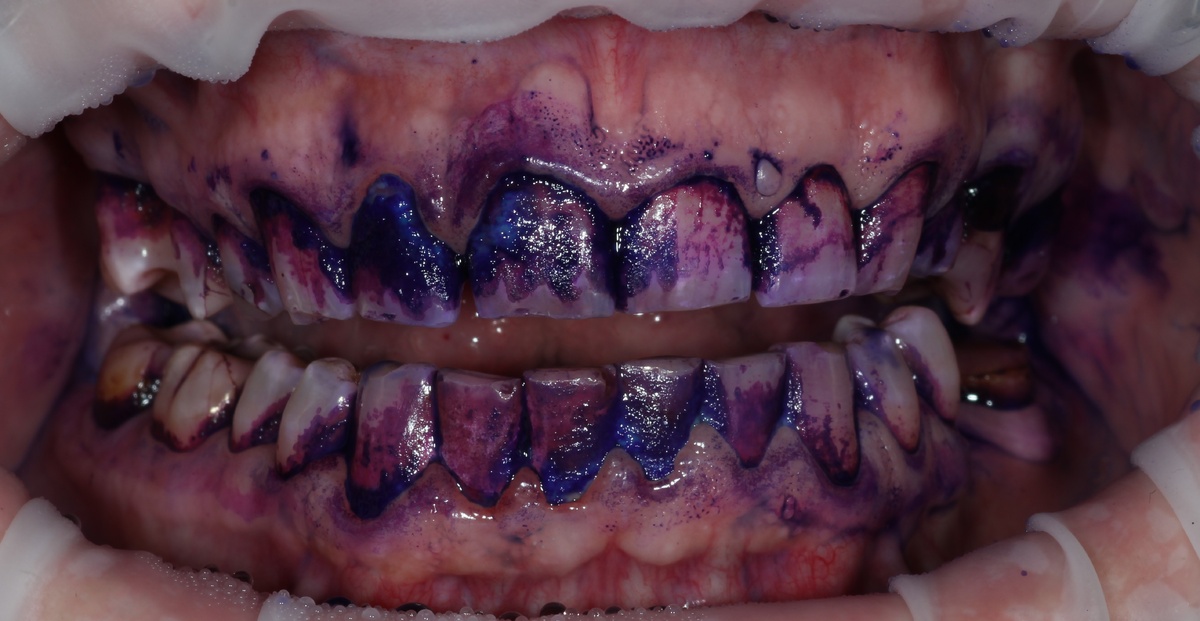

Этап 1: Диагностика реальных проблем

С помощью индикации налета выявили все зоны, которые пациент не может эффективно очистить дома. Стало ясно, где именно кроются основные проблемы.

Этап 2: Анализ техники домашней гигиены

Оказалось, что пациент использовал неподходящие инструменты и неправильную технику чистки. Годы неэффективных движений привели к хроническому накоплению налета в определенных зонах.

Этап 5: Контрольная проверка

Повторная индикация налета показала, насколько эффективна правильная техника. Проблемные зоны очищались практически полностью!